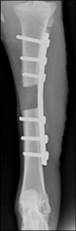

0�� 3���� 12W�� 24W�� 44W